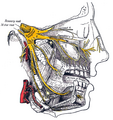

- Gray778 Trigeminal.png 563 × 599; 424 KB